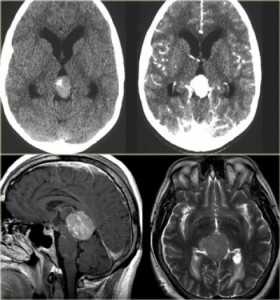

МРТ головного мозга. Сагиттальная и аксиальная Т1-взвешенные МРТ, аксиальная Т2-взвешенная МРТ и аксиальные КТ и Т1-взвешенная МРТ с контрастированием. Гигантоклеточная астроцитома с кальцификацией - внутрижелудочковая опухоль.